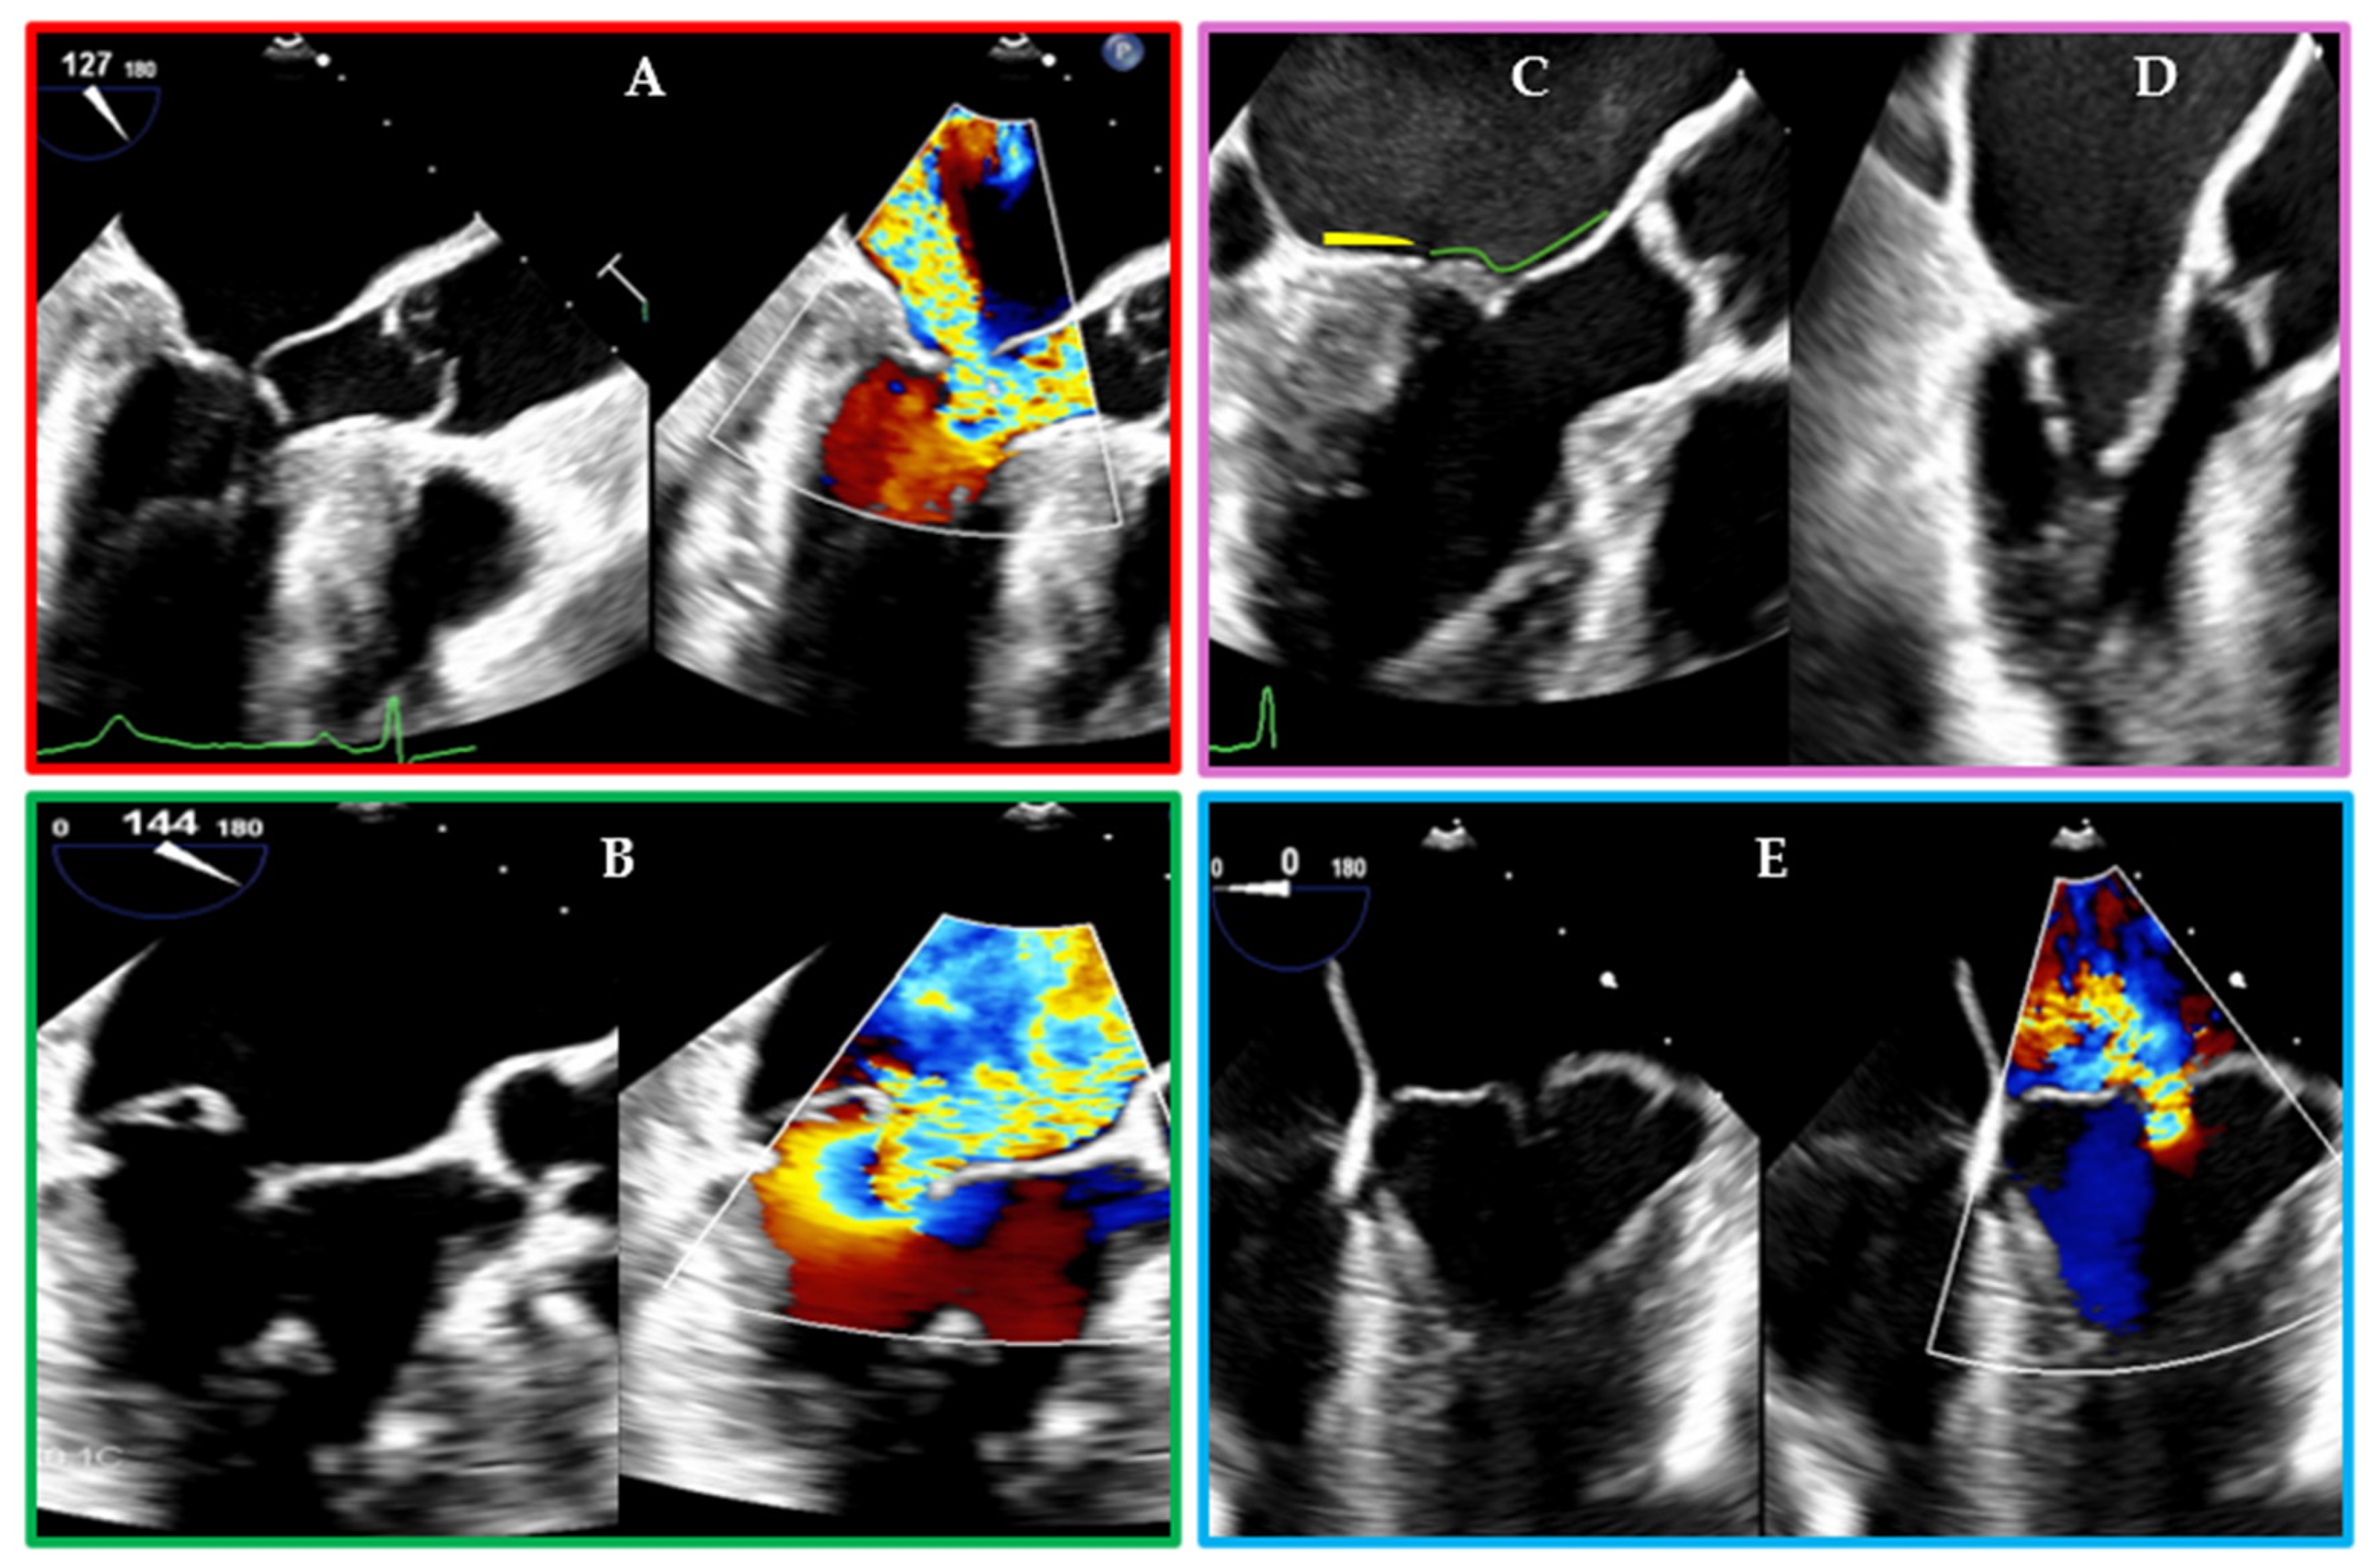

- Brugiatelli, L.; Rolando, M.; Lofiego, C.; Fogante, M.; Capodaglio, I.; Patani, F.; Tofoni, P.; Maurizi, K.; Nazziconi, M.; Massari, A.; et al. Transcatheter Mitral Valve Intervention: Current and Future Role of Multimodality Imaging for Device Selection and Periprocedural Guidance. Medicina 2024, 60, 1082. [Google Scholar] [CrossRef]

- Gheorghe, L.L.; Mobasseri, S.; Agricola, E.; Wang, D.D.; Milla, F.; Swaans, M.; Pandis, D.; Adams, D.H.; Yadav, P.; Sievert, H.; et al. Imaging for Native Mitral Valve Surgical and Transcatheter Interventions. JACC Cardiovasc. Imaging 2021, 14, 112–127. [Google Scholar] [CrossRef] [PubMed]